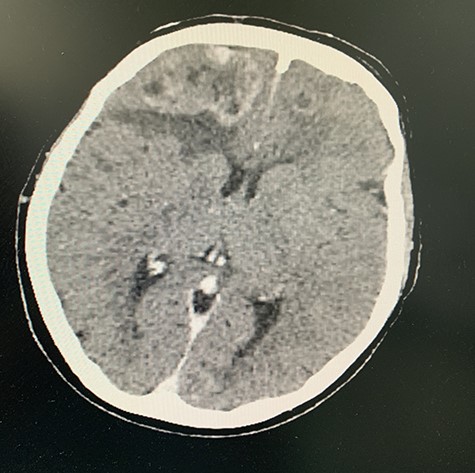

She was referred for urgent respiratory review and discussed at the respiratory Multidisciplinary team (MDT) meeting at a regional referral centre, where staging CT brain revealed six cerebral metastases with two large regions of vasogenic oedema. The metastases were bilateral, but more marked on the right, with the largest lesion in the anteroinferior right frontal lobe producing mass effect on the right lateral ventricle frontal horn and midline shift to the left of 5 mm (Figs 5 and 6). Staging bone scan revealed no bony metastases.